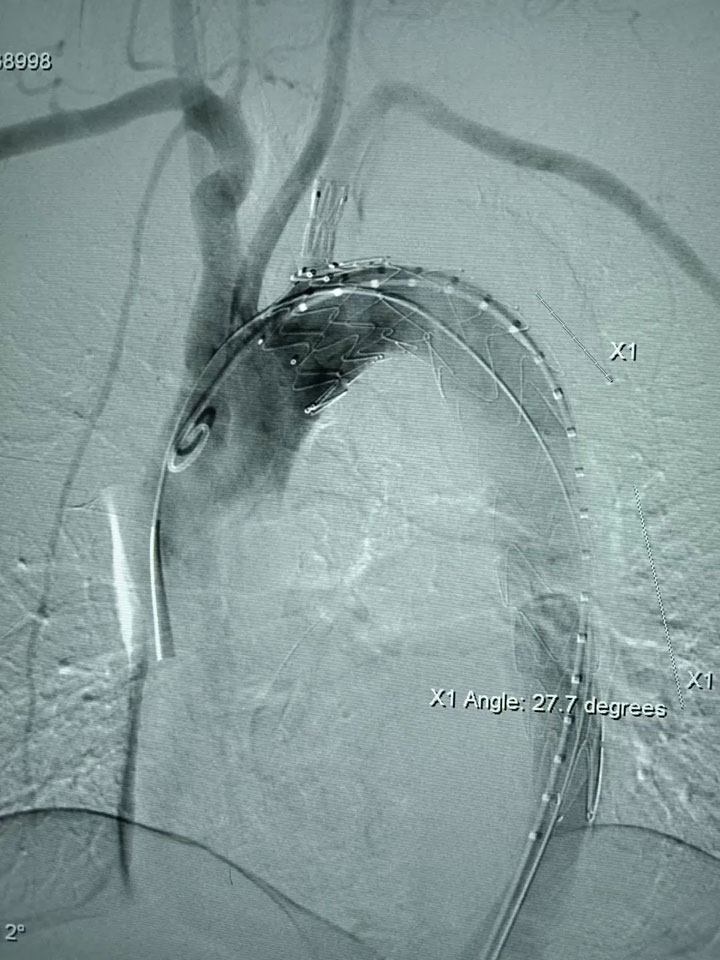

4个多小时的手术,犹如“刀锋上的芭蕾”,普外科医疗中心团队在毫米血管里“穿针引线”,开辟生命通道,顺利完成了锥动脉至颈总动脉的转流,之后又将一枚分支型支架成功置入主动脉夹层处,达到100%覆盖。桂锐主任团队小心谨慎,技高胆大,终于成功解除孙先生动脉夹层的危机,把他从死神手里“抢”了回来。